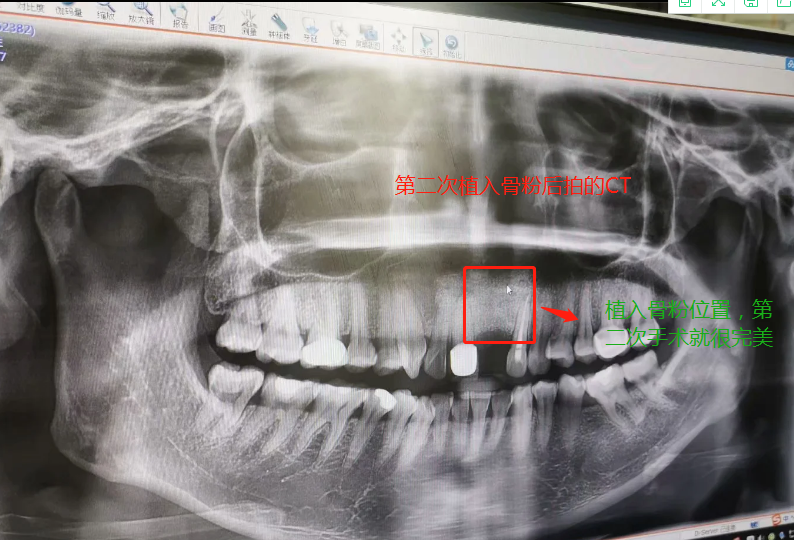

第二次做完植入手術(shù)后拍的CT

2019年7月27日做了種植骨粉手術(shù),在醫(yī)院要等半個(gè)小時(shí)留意一下是否有出血情況,沒有就可以回家休息。做手術(shù)是自己一個(gè)人坐地鐵來回的,勇敢吧。第一天嘴里都是血,第二第三天也是,臉也腫起來,也會(huì)有一點(diǎn)點(diǎn)骨粉掉出來,我那幾天都是喝粥和喝湯,第四天才敢吃飯,第七天傷口就好了,可以帶上臨時(shí)假牙,因?yàn)槲沂巧项€門牙,上顎骨頭密度沒有那么好,正常要等4個(gè)月左右,我的骨粉還是種植的,不是自身的骨頭,所以必須要等半年才能種種植牙。等到2020年1月26日去種植牙根的時(shí)候,那個(gè)主任已經(jīng)調(diào)去別的分店,第一次補(bǔ)完骨粉我就發(fā)覺里面還有個(gè)小洞,問醫(yī)生里面為什么有個(gè)洞的,醫(yī)生說沒事的。我打算去分店種植牙齒的,以為跟我那個(gè)醫(yī)生會(huì)比較了解我情況,后來那個(gè)的助理叫我不要去分店弄了,在這里安排個(gè)專家給我看。經(jīng)過專家的診斷,我還有個(gè)洞沒有補(bǔ)到骨粉,需要再做個(gè)補(bǔ)骨粉手術(shù)后等半年看看情況能不能種牙再說。我聽了真想哭起來,大門牙好不容易空半年可以種牙了,結(jié)果還要我補(bǔ)骨粉,還要等那么長(zhǎng)時(shí)間。經(jīng)過跟這家醫(yī)院醫(yī)生溝通和別的門診醫(yī)生回答,決定還是回到這家醫(yī)院做修復(fù),跟助理談了價(jià)格,他說就收取800元,補(bǔ)0.5克骨粉。于是就開始了第二次手術(shù),第一次手術(shù)補(bǔ)了0.5克骨粉(2個(gè)單位,0.25克為一個(gè)單位),第二次補(bǔ)了0.75克骨粉,本來是0.5克骨粉,醫(yī)生做手術(shù)的時(shí)候說還有點(diǎn)間隙,還需要0.25克骨粉,問我要不要加,我說加,就算要另外收費(fèi),我也要加,我的牙齒受的折磨太多了。我要好好弄好這顆牙齒,就收了800元,也沒有額外收0.25克的骨粉錢。我在這家口腔醫(yī)院花了6800元種植骨粉,第二次骨粉植入傷口比較大,醫(yī)生說恢復(fù)期要12天,確實(shí)7天傷口還是沒有恢復(fù)的很好。而且今年1月底爆發(fā)疫情,1月31日領(lǐng)導(dǎo)就讓我們上班,我們公司是做醫(yī)療設(shè)備。傷口都沒有完全康復(fù)就堅(jiān)持上班了。